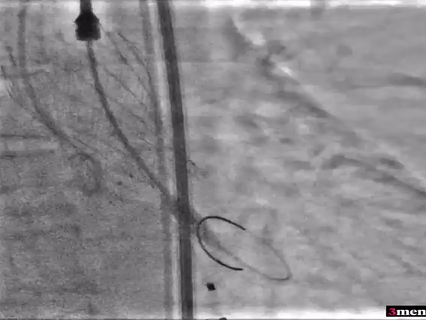

患者三手术过程

在放射科,超声科和麻醉科的通力协作下,顺利完成了术前准备,术者团队在术中谨慎建立轨道,根据主动脉根部造影的结果选择合适的跨瓣体位。

主动脉根部造影

球囊预扩

瓣膜定位

瓣膜释放过程

球囊后扩